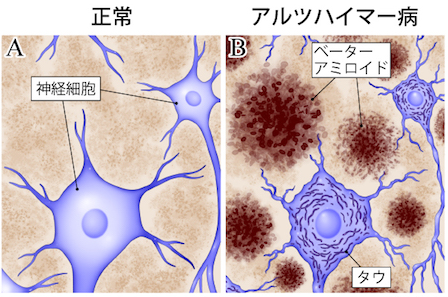

認知症は、脳のどのような変化によって起こるのでしょうか。

この章では、アルツハイマー病を中心に、現在もっとも研究が進んでいる「原因物質」や「神経細胞の変化」について整理していきます。

その中心的な役割を果たしていると考えられているのが、

- アミロイドβ(Aβ)

- タウたんぱく質

という2つの物質です。

これらが脳の中で“溜まる”ことで、神経細胞が障害されると考えられています。

■ アミロイドβとは? —— 発症の20〜30年前から蓄積が始まる

アミロイドβは、脳の神経細胞の外側にたまるたんぱく質です。

健康な脳でも日常的に作られていますが、

加齢や生活習慣、遺伝的要因などにより、排出のバランスが崩れると脳に蓄積しやすくなるとされています。

■ タウたんぱく質とは? ― 神経細胞の“内側”の異常

アミロイドβの蓄積が引き金になると、

次に起こるとされているのが タウたんぱく質の異常(凝集) です。

タウは本来、神経細胞の内部で構造を支える役割がありますが、

異常な形に変化すると“もつれ(タングル)”を作り、神経細胞を傷つけます。

● アミロイドβ:神経細胞の外側にたまる

● タウ:神経細胞の内側で凝集する

という違いがありますが、

両者は連動しながら神経細胞を障害すると考えられています。

■ 神経細胞が傷つくと、脳のネットワークが崩れる

脳は、無数の神経細胞がネットワークのようにつながり、情報をやり取りすることで働いています。

アミロイドβやタウが蓄積し神経細胞が死んでしまうと、